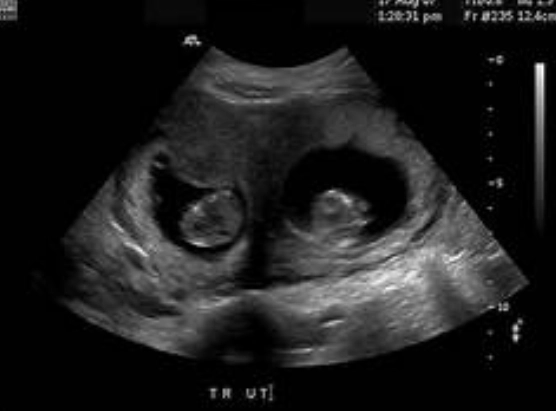

Can it detect twins at 1 month?

It's possible, but not reliable. You might see two gestational sacs, but at this stage, it's also possible for one sac to be hidden or for one sac not to develop further (vanishing twin syndrome). Twin confirmation is much more solid around 8 weeks.

- 6-7 Weeks: This is when you're more likely to see the fetal pole and possibly detect cardiac activity. For many, this is the first "real" scan that provides significant reassurance.

- 8-10 Weeks: The standard first prenatal ultrasound for many. You'll see a baby that looks more human, with a clear heartbeat. Measurements are taken for accurate dating.